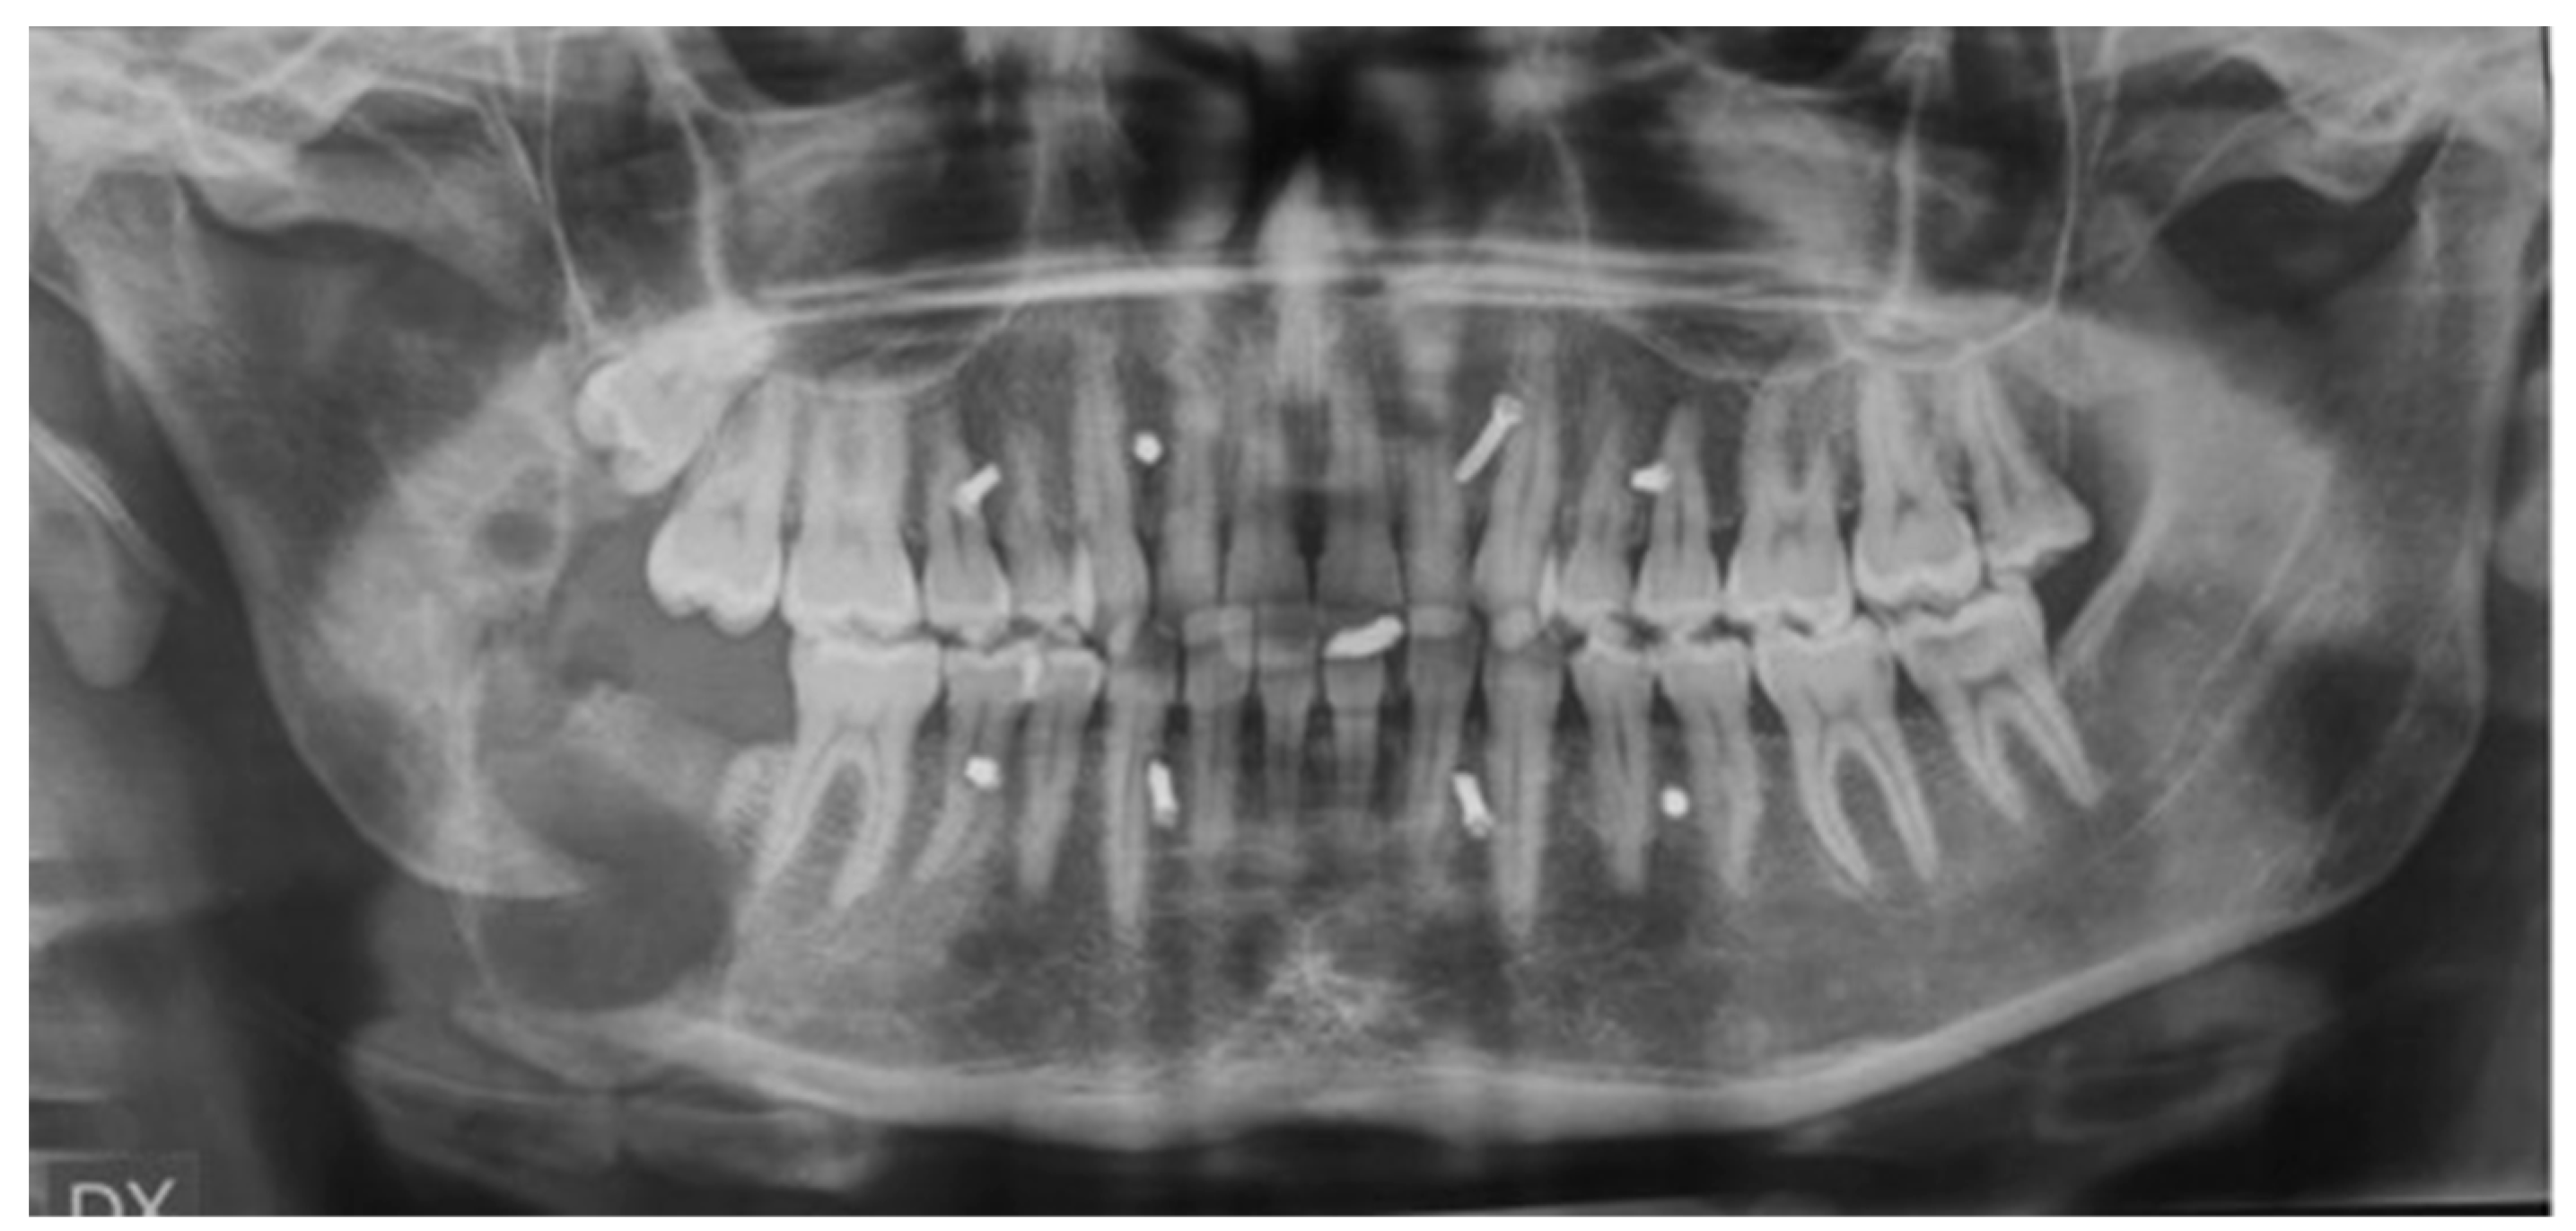

2.6. Patient #2

2.9. Results Case #2